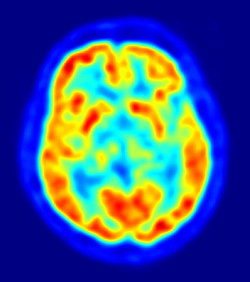

Un nuevo descubrimiento cuestiona la teoría predominante para tratar el Alzheimer

Un estudio dirigido por la Universidad de Cincinnati, en Estados Unidos, en colaboración con el Instituto Karolinska de Suecia, afirma que el tratamiento de la enfermedad de Alzheimer podría residir en la normalización de los niveles de una proteína cerebral específica llamada péptido beta-amiloide. Esta proteína es necesaria en su forma original y soluble para mantener el cerebro sano, pero a veces se endurece formando "piedras cerebrales" o cúmulos, llamados placas amiloides.